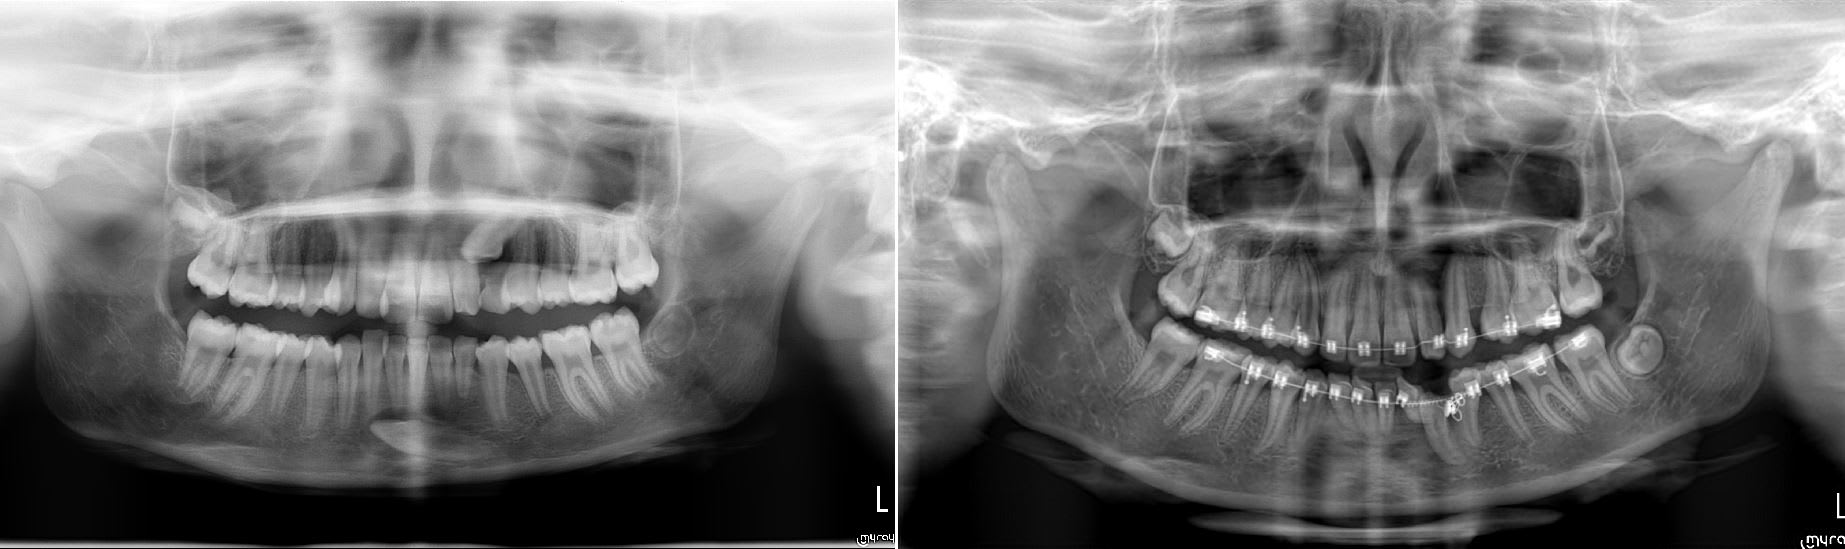

L'apex de la 43 est en bonne position, ce qui veut dire que tu n'a qu'a faire un mouvement de tipping pour redresser la dent.

J'ai quasi le même cas en cour :-) .

La patiente avait besoins d'un traitement ortho ( une canine impacté en haut aussi ) donc j'ai intégré la traction avec l'appareillage et pas besoin d'utiliser de minivisse.

Par contre c'est long prévoir minimum un ans pour redresser la canine.

Plus d'un ans pour en arriver là.

Impacted lbrnqb - Eugenol